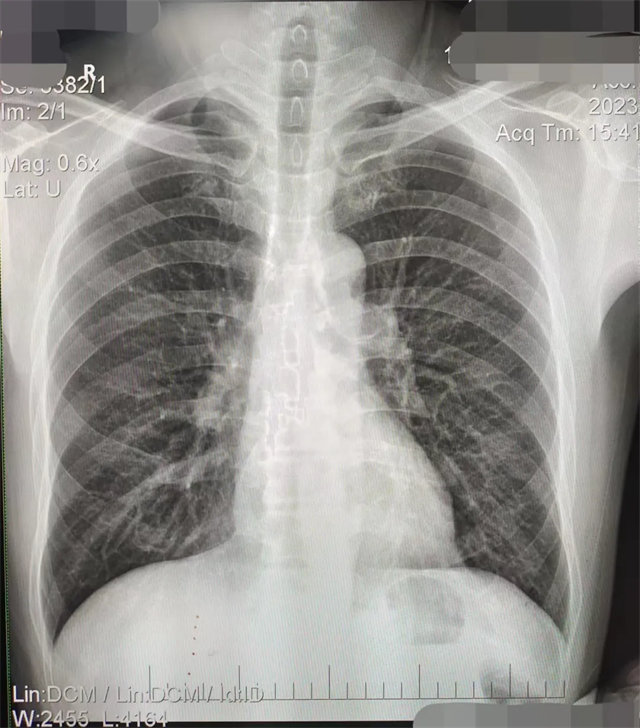

缺陷:左肩胛骨部分與左肺野重疊。

解決:使患者左肩旋前緊貼成像件重新曝光。

缺陷:肩胛骨未完全拉離肺野,吸氣不完全,存在金屬偽影遮擋,略有聳肩,且肺尖顯示不好,圖像顆粒感較強,管電流量不夠,信噪比偏低。

解決:去除金屬物品后,按標準體位,使患者雙肩旋前與前胸一并緊貼成像件,適當(dāng)調(diào)高mAs,然后深吸氣后屏氣曝光。